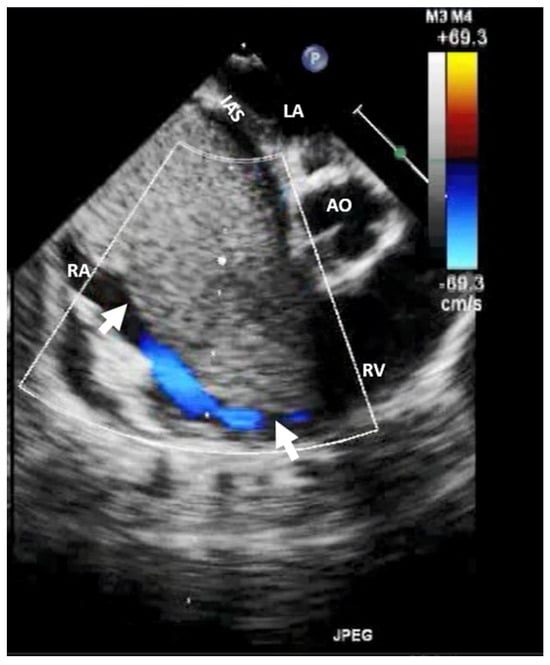

It can be used as a screening imaging method, but right heart tumors could be an incidental finding during a routine echocardiographic examination. This imaging technique is widely available (accessible), portable, and easy to perform, even at the patient’s bedside and in those who are hemodynamically unstable. It is safe, repeatable, cost-effective, and has a good spatial resolution (higher with TEE) and an excellent temporal resolution. For imaging small, highly mobile masses (<1 cm) or masses arising from valves, it is the optimal imaging modality [4]. TEE is more sensitive at identifying tumors smaller than 5 mm compared with TTE. Therefore, compared with TTE, TEE is better for the detection, location, and mobility of cardiac tumors and equivalent in the assessment of hemodynamic impact, compromising the compression/destruction/distortion of cardiac structures [12]. In some cases, the mass effect of a non-cardiac tumor severely compromises cardiac hemodynamics (Figure 1).

Two-dimensional transthoracic echocardiography (apical 4-chamber view) with color Doppler showing external compression of the free right ventricular wall (arrow) in a patient with hepatomegaly due to a hepatic tumor, which explains hemodynamic instability (similar to a localized cardiac tamponade). AO, aorta; IAS, interatrial septum; LA, left atrium; LV, left ventricle; RA, right atrium; RV, right ventricle.